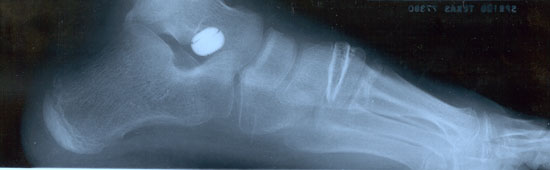

As seen in the photos above of the

x-rays, you can see the serious collapse in the foot before

treatment. In the photo on the bottom, we see an x-ray with

correction. Even though many doctors will still say that flatfeet do

not need to be treated, we know that this is not the case and the

current biomechanical literature now strongly supports treatment of

severe cases. In fact, this condition accounts for significant

skeletal problems later in life including: low back pain, knee joint

degeneration, increased risk of knee injuries, lower extremity pain,

and ankle problems.